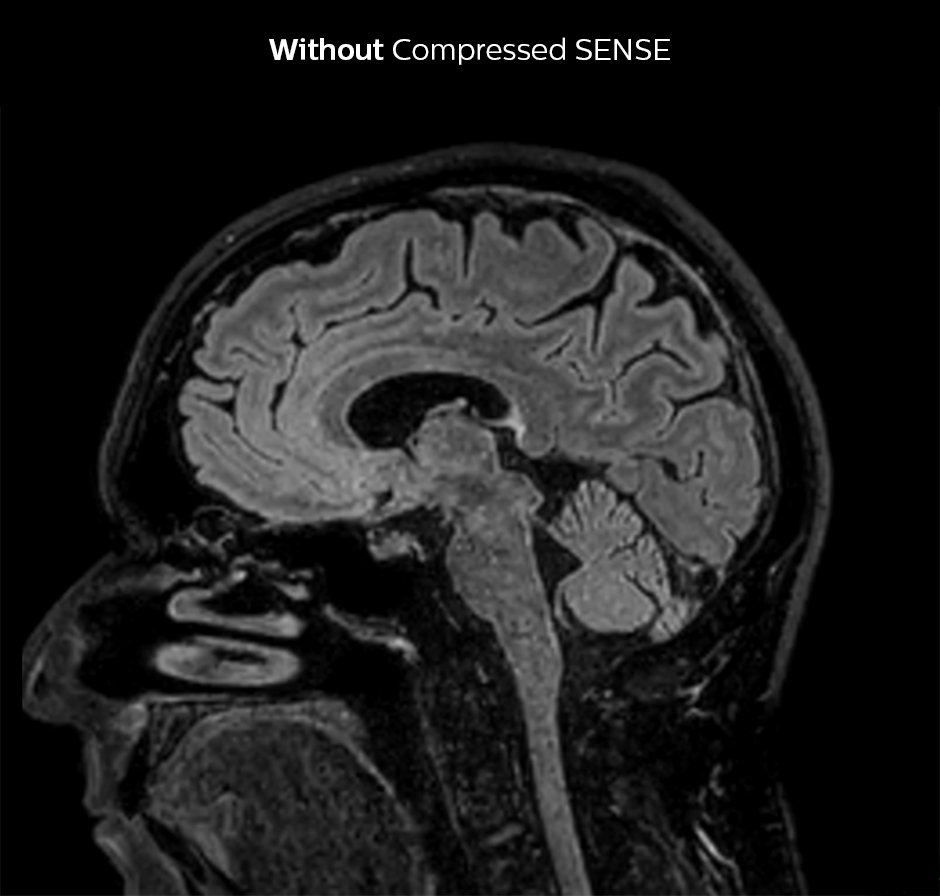

Shorter scan time in brain

Compressed SENSE allows 28% shorter scan time with the same spatial resolution.

3D FLAIR brain WITHOUT Compressed SENSE

3D FLAIR, scan time 5:02 min, voxel size 1.1 x 1.1 x 1.1 mm, Ingenia 1.5T.

3D FLAIR brain Compressed SENSE factor8

3D FLAIR, scan time 3:36 min, voxel size 1.1 x 1.1 x 1.1 mm, Ingenia 1.5T.